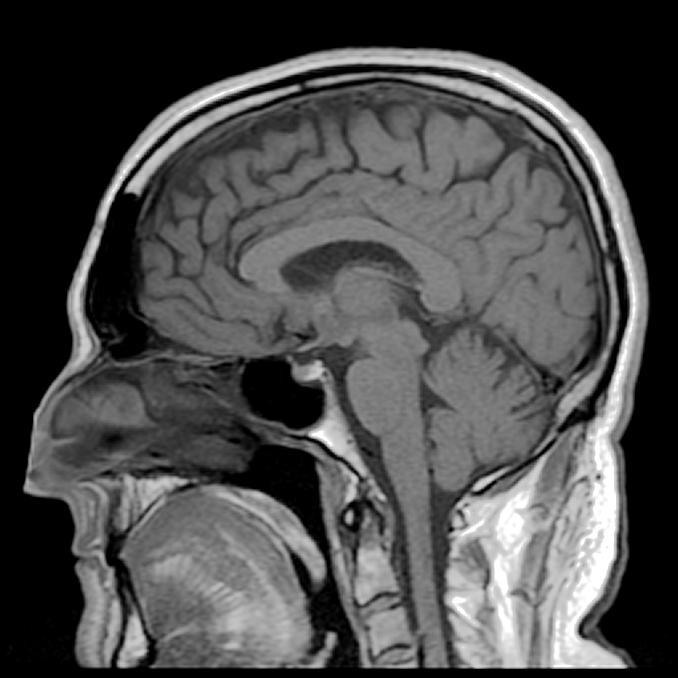

2023年06月17日失去記憶的人生是什麼模樣?看看83歲英國前音樂家Clive Wearing就知道了。他患有罕見的順行性失憶症(Anterograde Amnesia),記憶只能維持7到30秒。每過幾秒鐘,他就會忘記自己身處哪裡、現在是何年何月,就像剛剛從一場夢中醒來一樣。

▼1985年時,Clive在一場演奏會後小睡片刻,醒來時發現兒子站在面前,但他卻想不起兒子的名字。從那一天開始,他的世界改變了。他去醫院接受檢查,確診感染單純皰疹病毒,這種病毒入侵他的大腦,損害他的神經,漸漸將他的記憶清空。